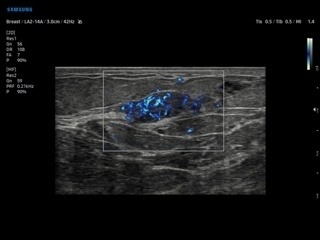

- Эластография: Elastoscan, E-Strain, E-Cervix;

- S-Detect для молочной железы и щитовидной железы;

- Elastoscan — программы эластографии для исследований щитовидной железы, молочной железы у женщин и предстательной железы у мужчин;

- E-Strain — полуколичественный анализ индекса Strain Ratio в режиме компресионной эластографии;

- S-Detect Breast — программа автоматического обнаружения и анализа образований молочной железы у женщин, измерение и классификация по системе BI-RADS;